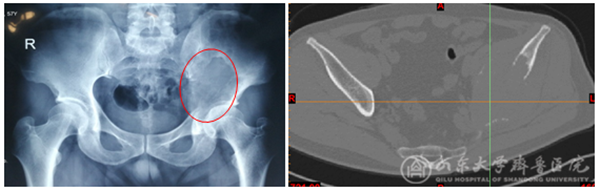

术前X线平片和CT可见肿瘤累及左侧髋臼及髂骨(1+2区),明显影响左髋关节的负重

CT数据生成三维模型并模拟手术切除